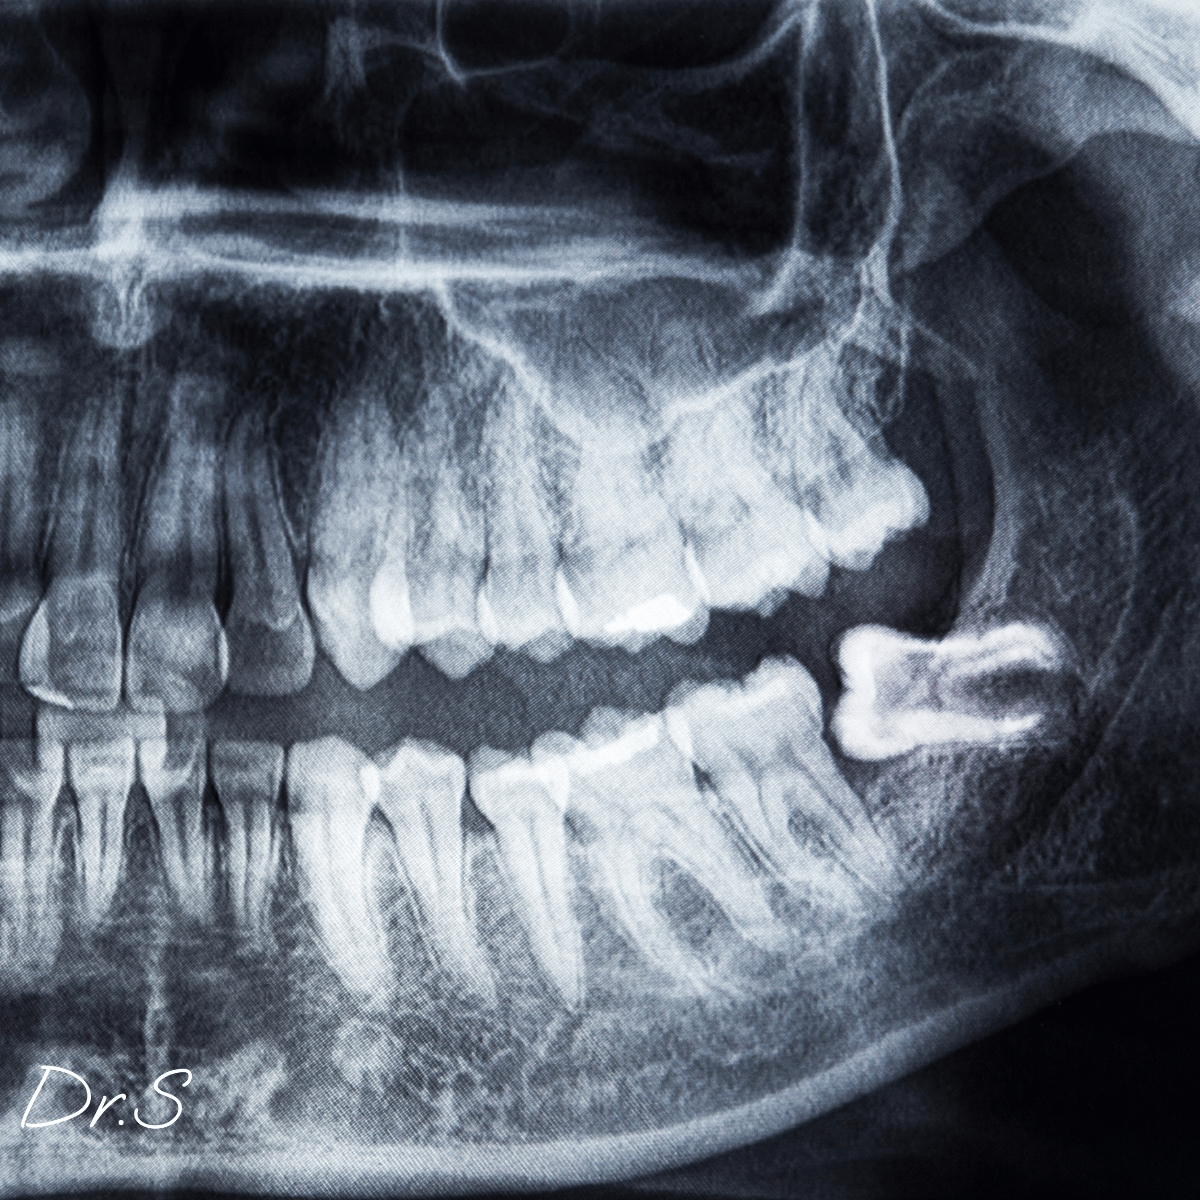

Il est aussi possible de ne pas développer de dents de sagesse. Cette agénésie, liée à l’évolution et à la réduction de la taille des mâchoires, est bénigne ; une radiographie panoramique confirme l’absence de germes.

Le germe apparaît vers 9–10 ans ; la couronne se forme autour de 12 ans ; les racines se développent ensuite, et l’éruption peut s’étaler jusqu’à environ 25 ans. La vitesse dépend de la biologie individuelle et de la place disponible.

Consultez en cas de douleur, gonflement, mauvaise haleine, difficulté à ouvrir la bouche ou infections répétées autour d’une dent demi-incluse. Un examen clinique et une radiographie (panoramique ou CBCT) orientent entre simple surveillance, désinfection locale ou extraction.